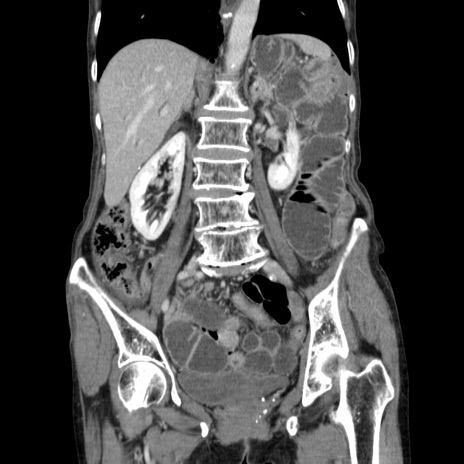

症例25(冠状断像)

【症例】80歳代女性

【主訴】胸のつかえ感

【現病歴】約9時間前に食後から胸のつかえた感じあり、嘔吐あり、来院。

【既往歴】胃癌(全摘)、胆摘、虫垂炎

【身体所見】心窩部に圧痛あり、反跳痛なし。

【データ】WBC 5700、CRP 0.05